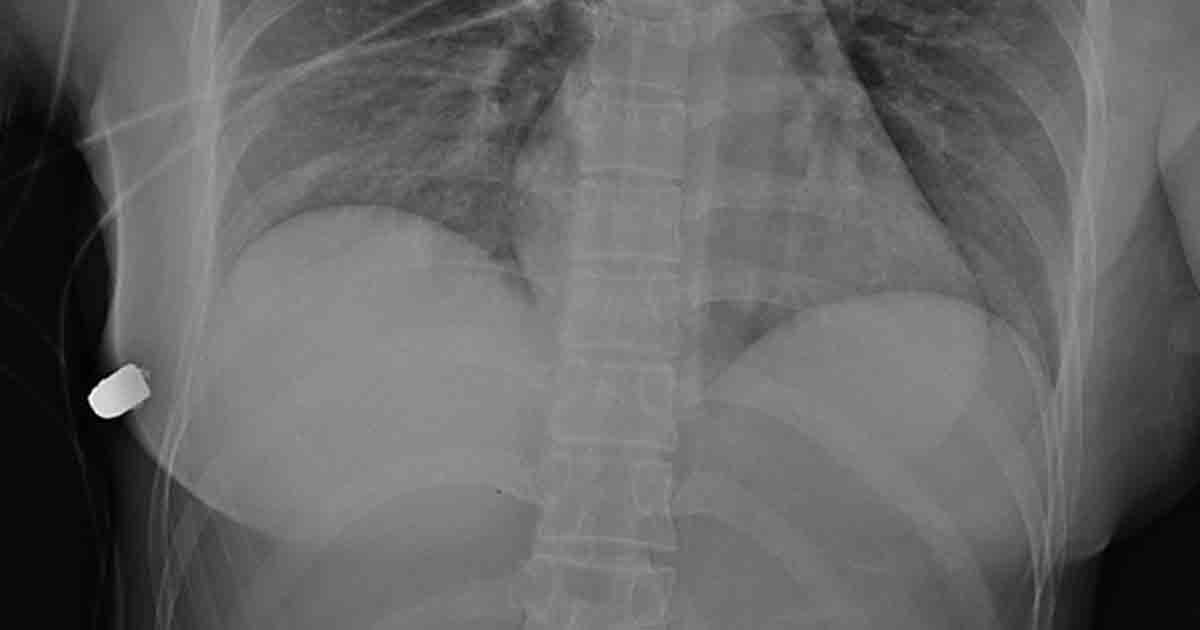

As the operation goes, medics found a hard, bullet-like object in the woman’s right lower anterior thoracic wall below the right breast.

Using trauma radiographs, medical experts were able to find the bullet in the right lateral thoracic wall, a fractured rib and air bubbles in the left breast, and concluded that the bullet traveled from the left breast to the right thoracic wall.